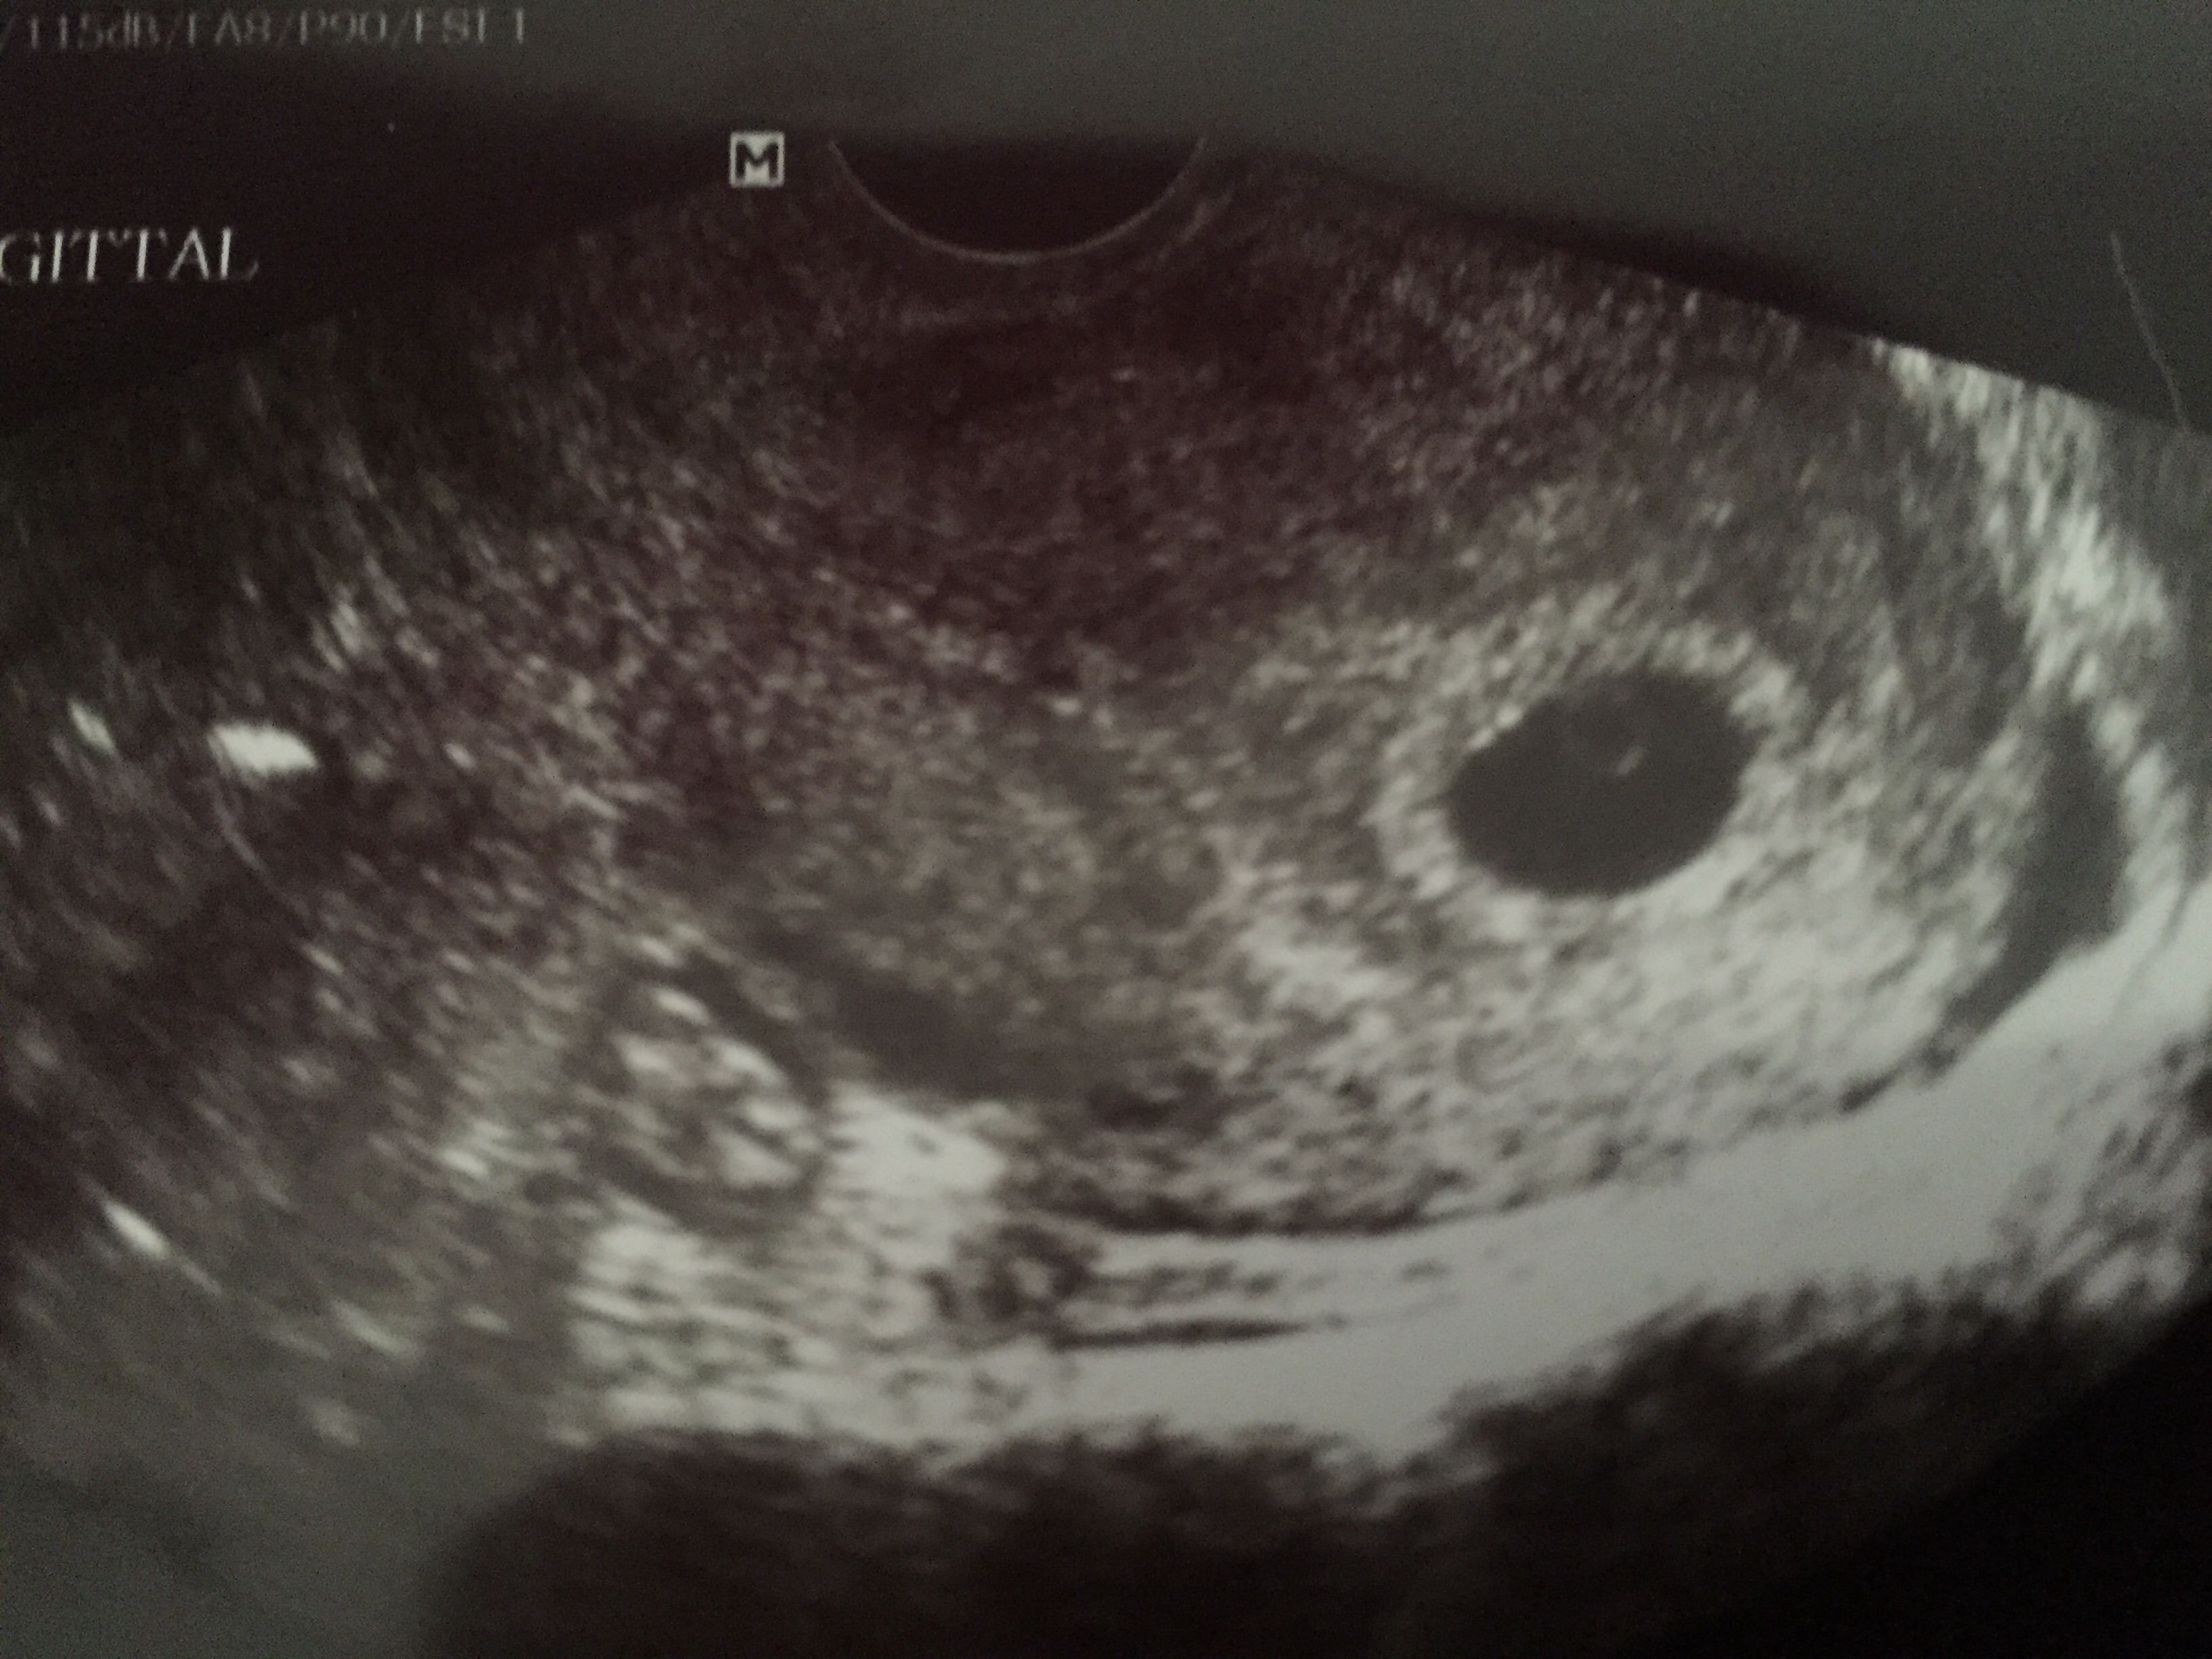

I just came back from a place where they give free ultrasounds for early pregnancy (through a church type clinic). I am 5 weeks 6 days today. Everything is just fine with the baby heart rate at 95 but she saw two sacks. She even said she saw a heartbeat in the second one. Spent 15 min trying to capture the heart rate and gave up saying it may be blood which is common in early pregnancy... What!? She said there is definitely two sacks but I only saw one little circle in one of them and nothing in the other. Does that sound like a cyst or a twin? The other "sac" was smaller than the first. (Attaching a pic of the sac with a measure able heart rate.) The other sac was on the other side (which she said was the correct placement for a twin) but I just didn't see anything and have had cysts before... Anyone with experience with either of these? I'm quite nervous now.